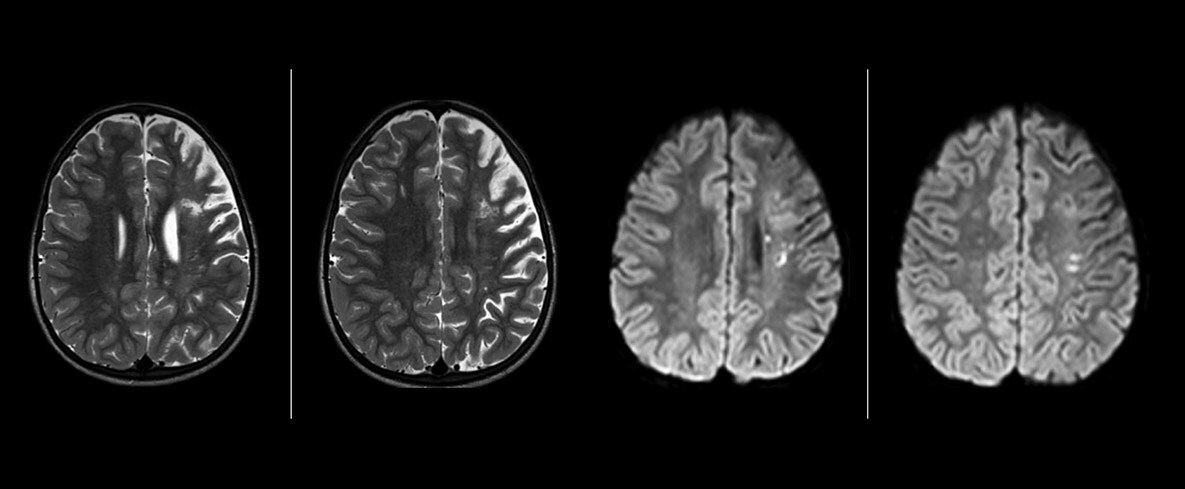

“SWIp helps us identify blood or blood products, calcification, and diseases that affect the vascular system,” says Dr. Miller. “In children with traumatic brain injuries, it highlights areas that are injured, better than some of the previous techniques that we were using. These children often have micro-injuries that cause small amounts of blood or tissue damage. Adding SWIp helps us to better characterize the extent and nature of the injury. Having characterized an injury to the extent of what’s possible supports our diagnostic confidence.”

“I would definitely recommend other users to implement SWIp. We initially added the SWIp sequence following a lot of support for its utility in the literature. Then we directly compared SWIp to the 2D gradient echo sequences that we were using. After a good amount of clinical experience in seeing its benefits, we were confident to replace the old sequences with SWIp. It gives us a better assessment of the physiological processes of the brain that were less apparent on our previous imaging sequences,” says Dr. Miller. “SWIp is now a routine sequence for imaging traumatic brain injury patients at PCH, and it’s episodically added for patients who have intracranial vascular abnormalities.”

“I believe SWIp is rapidly becoming the standard in imaging traumatic brain injury, because of its high sensitivity to venous blood products. SWIp may even help attract patients; our neurosurgeons often ask to have the patients imaged on our scanners with highly sensitive techniques like SWIp. There’s also a growing application of SWI sequences in other vascular abnormalities because of the possibilities around physiological assessment of the brain than just a standard structural imaging.”